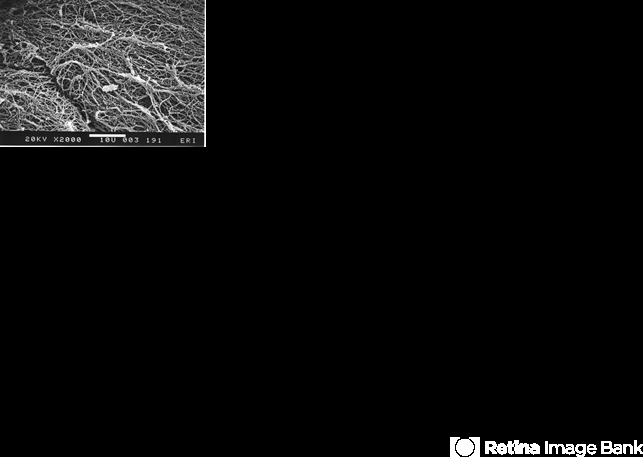

- scanning EM, posterior vitreous cortex, collagen fibrils, vision degrading myodesopsia

- EM lab, Eye Research Institute of Retina Foundation, Boston, MA

- Scanning electron microscopy demonstrates the dense packing of collagen fibrils in the posterior vitreous cortex. To some extent this arrangement is exaggerated by the dehydration that occurs during specimen preparation for scanning electron microscopy (bar = 10 µm).